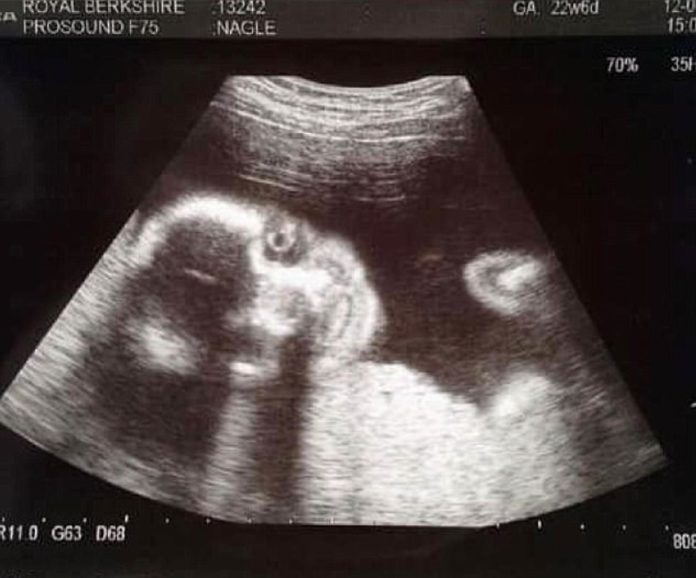

No, prva fotografija sina koju je dobila kada je bila trudna 20 sedmica, nije oduševila 25-godišnju Sophie Nagle.

Dječak sada ima dvije godine, a njegova majka odlučila je javno podijeliti fotografiju s ultrazvuka koja nije šokirala samo nju već i tehničarku koja ju je snimala.

“Odlučila sam se na 3D ultrazvuk, no kada sam vidjela prvu fotografiju malo je reći da sam se šokirala. Ostale smo zaprepaštene i ja i tehničarka koja je radila ultrazvuk”, ispričala je ova majka.

Na snimci se dječak smiješi, no to nije osmjeh kakav biste voljeli vidjeti jer više podsjeća na Jokera iz Batmana nego nevino novorođenče.